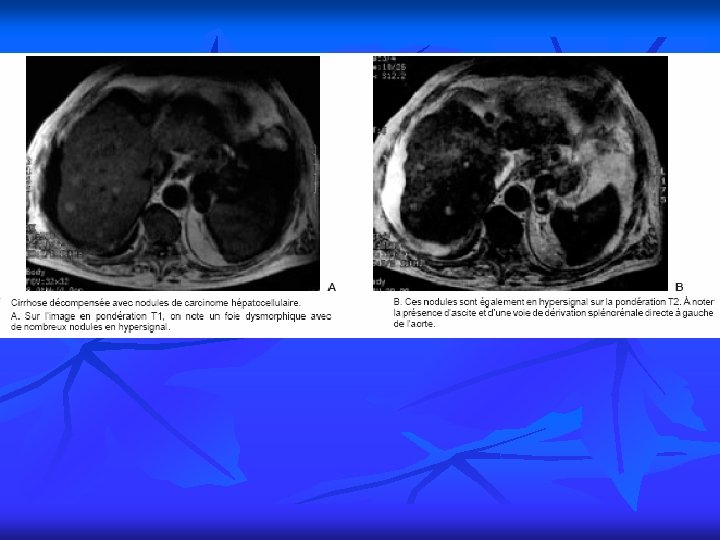

PRINCIPALES INDICATIONS 12 4. Imagerie du foie, des voies biliaires et du pancréas n Pathologie du foie Tumeurs bénignes Tumeurs malignes Cirrhose